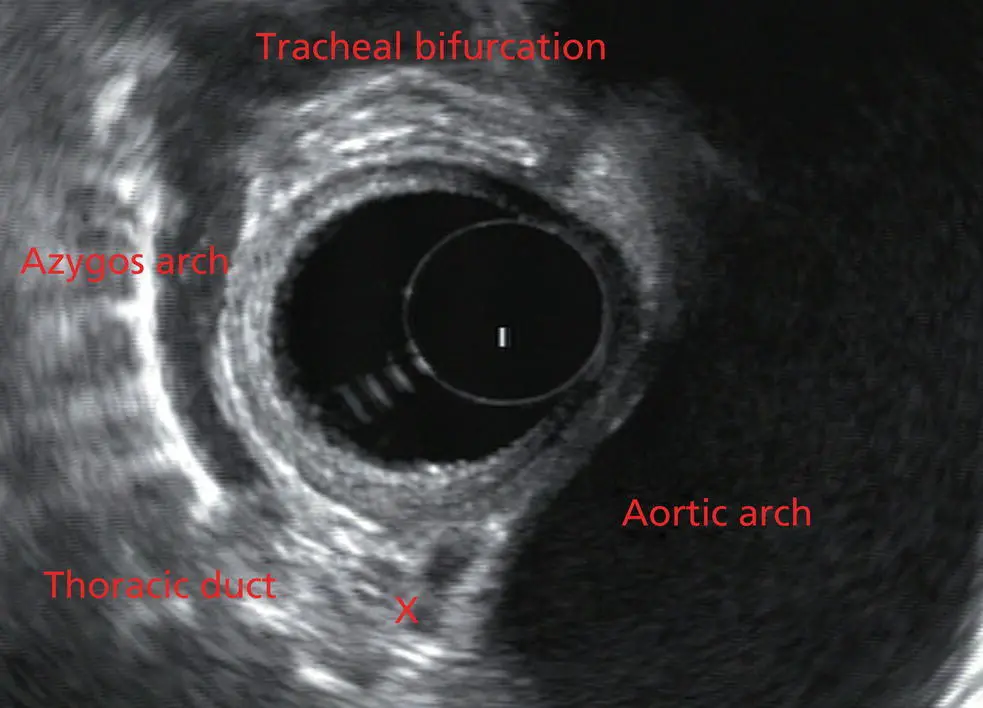

As the scope is withdrawn the bronchi come together at the carina. At or just proximal to this level the azygos arch ( Figure 2.6) can be identified traveling superiorly and laterally into the superior vena cava. This is also the area of the aortopulmonary (AP) window at approximately 2 o’clock.

Figure 2.6 Radial array image at the level of the azygos arch.